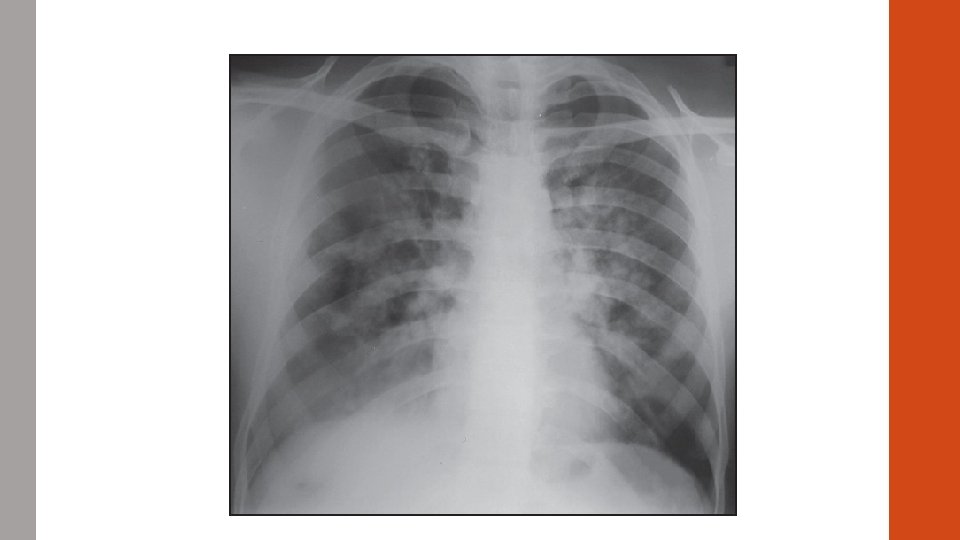

#5 CASE STUDY A 31 year old smoker presents to the ED with acute onset shortness of breath. Symptoms began ~2 hours prior to arrival. Syncopal event en route. She also endorses chest pain. T 98. 0 HR 125 BP 90/55 Sp. O 2 85% on 6 L NC.

A R L B

ABG 7. 56/20/56/24 p. H/CO 2/HCO 3

Diagnosis? Massive PE!